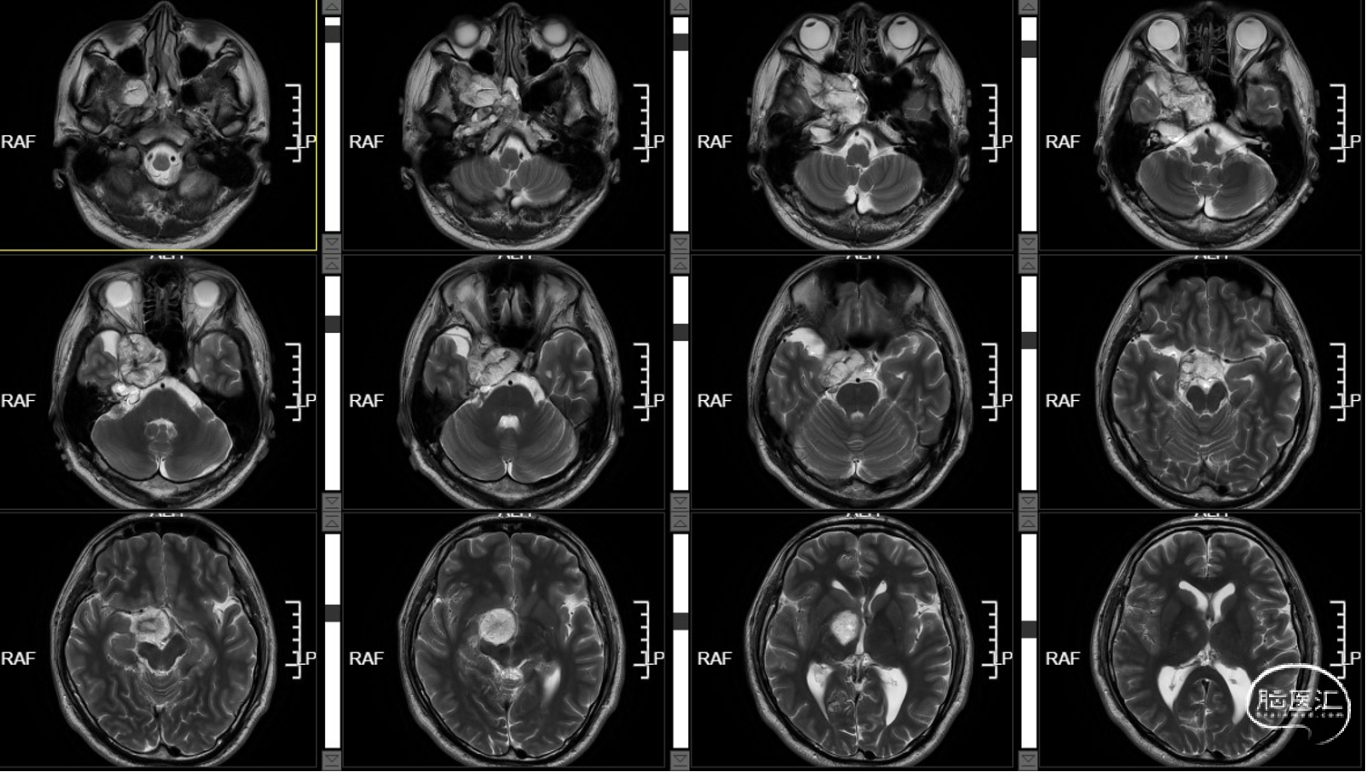

外院MR示:右侧颞底、桥小脑角区及鞍内占位,考虑表皮样囊肿伴破裂可能。